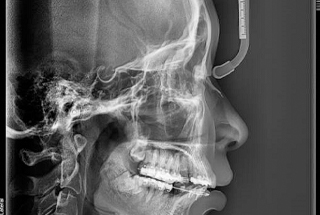

CBCT stands for Cone-beam (or Conebeam) Computed Tomography. It takes highly detailed, three-dimensional images that provide much more information than a standard digital X-Ray. For example, instead of just producing images of the bones and teeth, it also shows nerves and connective tissues.

Essentially, a CBCT machine is a super-powered X-Ray. It uses a cone-shaped beam of radiation to produce images of the jaw, teeth, and nearby areas. Although it emits more radiation than a standard X-Ray, it uses less than a regular CT machine that you would find in a hospital. The scanning process is extremely safe for most patients.